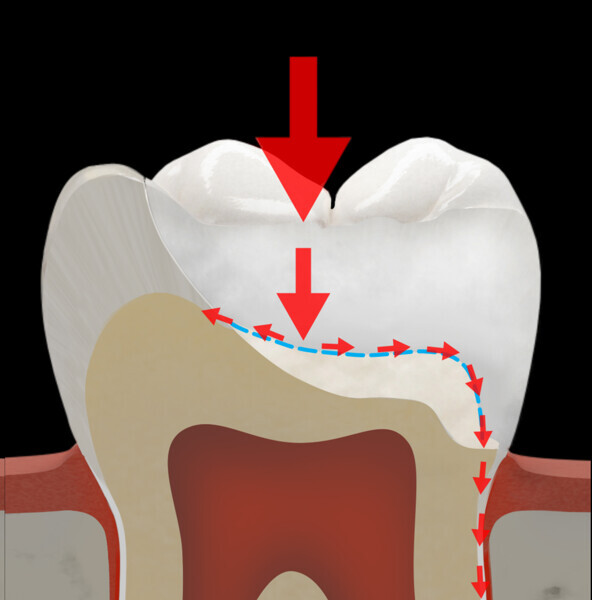

The first step in the MiCD Fiber Filling 4R protocol involves recognising the tooth status, existing occlusal forces and potential tooth preparation design. This starts with a thorough assessment of the patient’s dental condition, occlusal patterns and occlusal contact mapping using articulating paper of suitable thickness and the progressive colour transfer technique. Every tooth has its own stress pattern, and each contact location on a tooth behaves differently under stress. Recognising these patterns is vital for designing a restoration that avoids potential failure in the long term. Additionally, designing the restoration with tooth and restoration reinforcement in mind helps address specific structural requirements and challenges, ensuring that the final outcome is both functional and durable.

The second step focuses on reinforcing the restoration through careful fibre and FRC selection and placement. Tooth preparation should involve minimal removal of tooth structure to preserve as much natural tooth as possible in preparing the cavity for the restoration. Fibres or layers of FRC (flowable, paste, cube, etc.) are then strategically placed within the prepared tooth and composite material to reinforce areas susceptible to high stress and occlusal forces based on occlusal contact mapping. This strategic selection and placement of fibres and layers of FRC is crucial for enhancing the strength and longevity of the restoration.